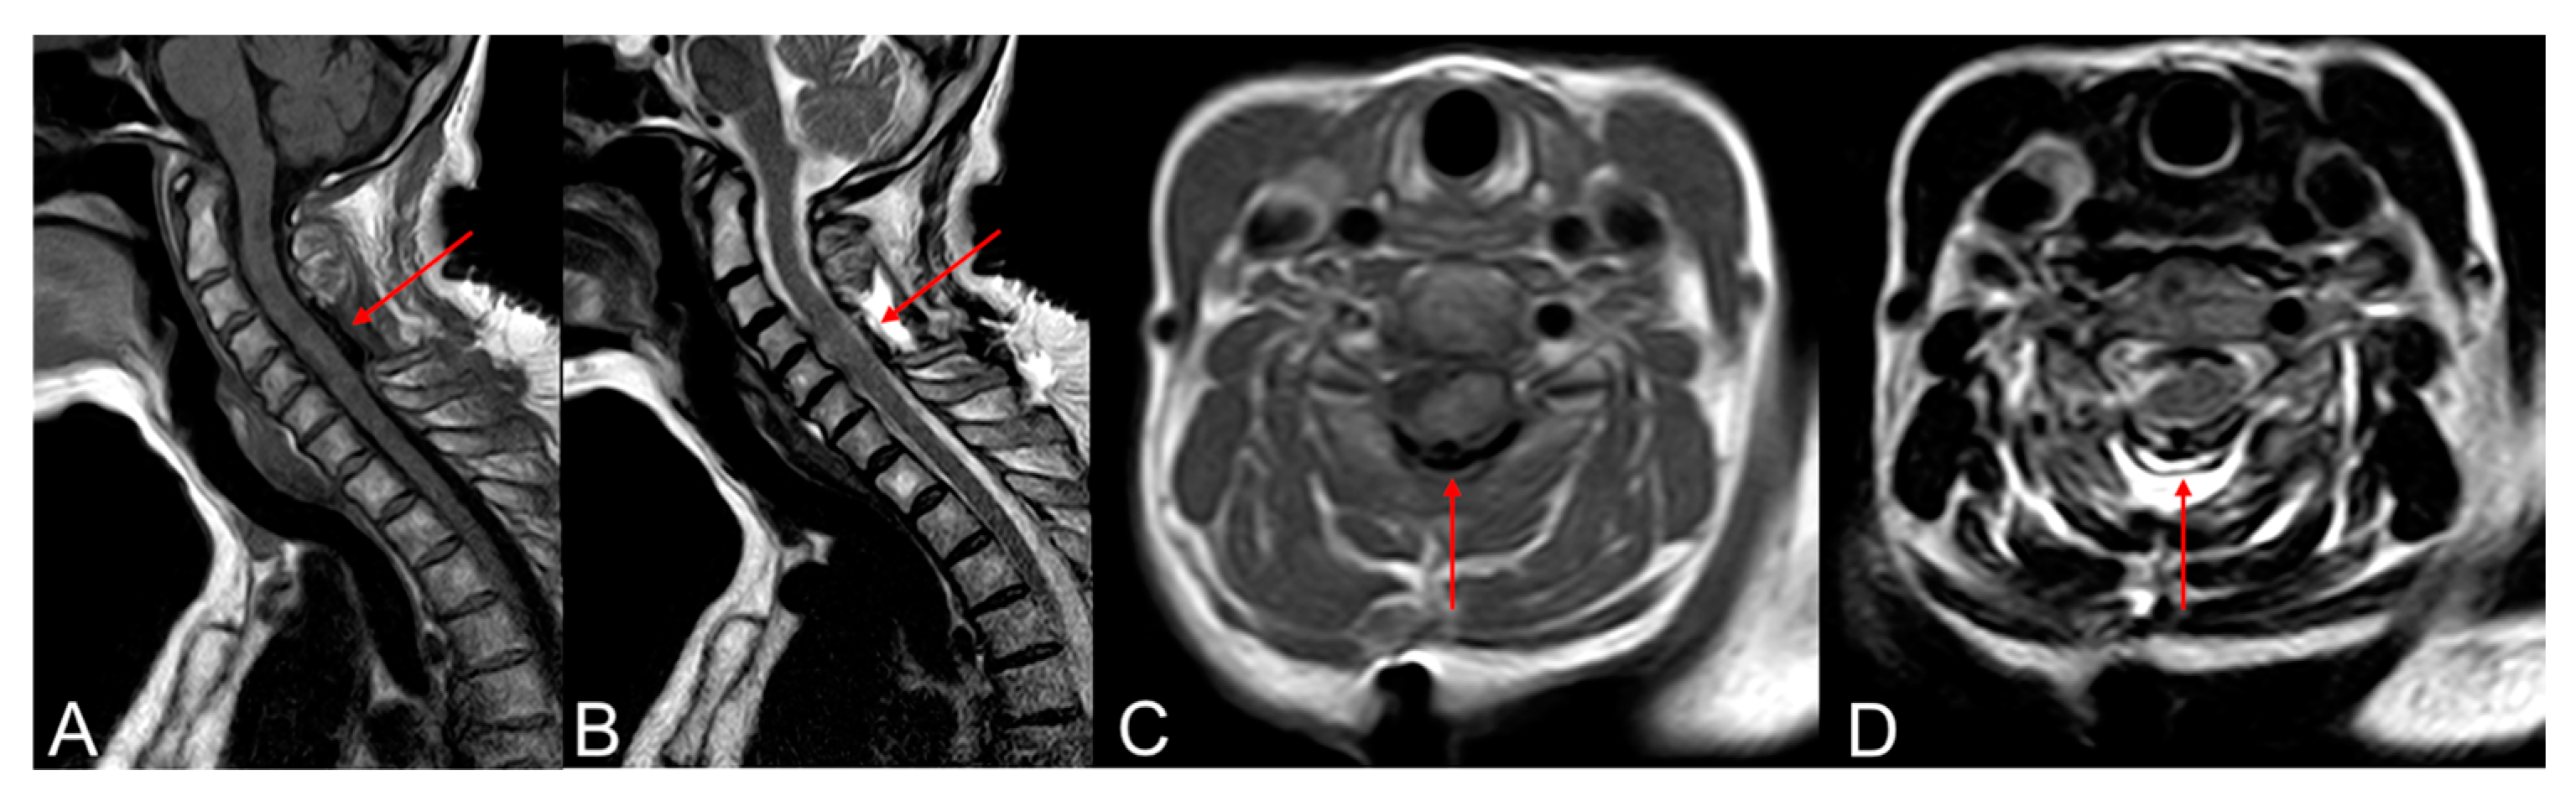

Numerous investigations have examined the efficacy of these clips. Non-penetrating titanium clips offer a dural closure that exhibits immediate hydrostatic strength like intact dura, whereas suturing with either material proved notably less resilient. Moreover, the application of titanium clips demonstrated a more rapid procedure compared to suture repair [20]. Kiyoshi I. et al. conducted experimental studies comparing the hydrostatic pressure tolerance between non-penetrating titanium clips and conventional sutures. They found that the leakage pressure in the non-penetrating titanium clip group was 1.8 times higher than that in the suture group. Furthermore, the clips did not create holes, and fluid leakage occurred between them, while in the suture group, leakage occurred at the suture holes. This led them to conclude that the interrupted placement of non-penetrating titanium clips allows for dural closure without creating holes, leading to improved initial leakage pressure and reduced postoperative CSF leakage following spinal surgery [21]. Furthermore, clips suture for dural repair in a relevant animal model displayed significantly less extensive acute and chronic inflammation, foreign body reactions, and meningoneural adhesions compared to suture [22]. Studies evaluating the metallic artifacts caused by the AnastoClips® in postoperative neuroimaging have concluded that no significant alterations in evaluation quality occur postoperatively (Figure 2) [23].

Figure 2. Titanium non-penetrating clips in the postoperative MRI (arrow). The use of clips does not compromise the quality of postoperative MRI images and does not show significant artifacts. T1 sagittal and axial plane (A,C). T2 sagittal and axial plane (B,D).